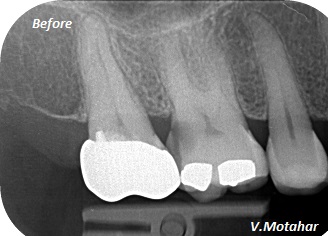

Root Canal treatment on Lower molar tooth immediate after the Root Filling!

before

after